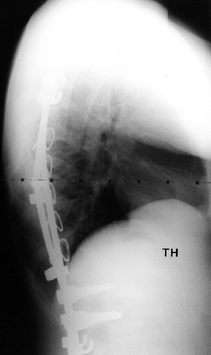

as for the type II to IV curve patterns. (Fig. 156.25, Fig. 156.26, Fig. 156.27, Fig. 156.28, Fig. 156.29 and Fig. 156.30 show typical cases.)

![]() |

|

Figure 156.25. Preoperative AP radiograph of the right thoracic curve.

Figure 156.26. Postoperative AP radiograph of the right thoracic curve.

Figure 156.27. Postoperative lateral radiograph of the right thoracic curve.

Figure 156.28. Preoperative AP radiograph of type I thoracic and lumbar curves.

Figure 156.29. Postoperative lateral radiograph of type I thoracic and lumbar curves.

Figure 156.30. Postoperative AP radiograph of type I thoracic and lumbar curves.s